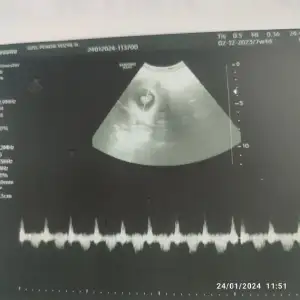

Aynen. Dolucak güzel olucak amaMinişler nasıl da büyüyorlar. Bu da bizim bugunki ultrasonumuz. Bu ay artık böyle görüntülerle dolacak burasi inşallah